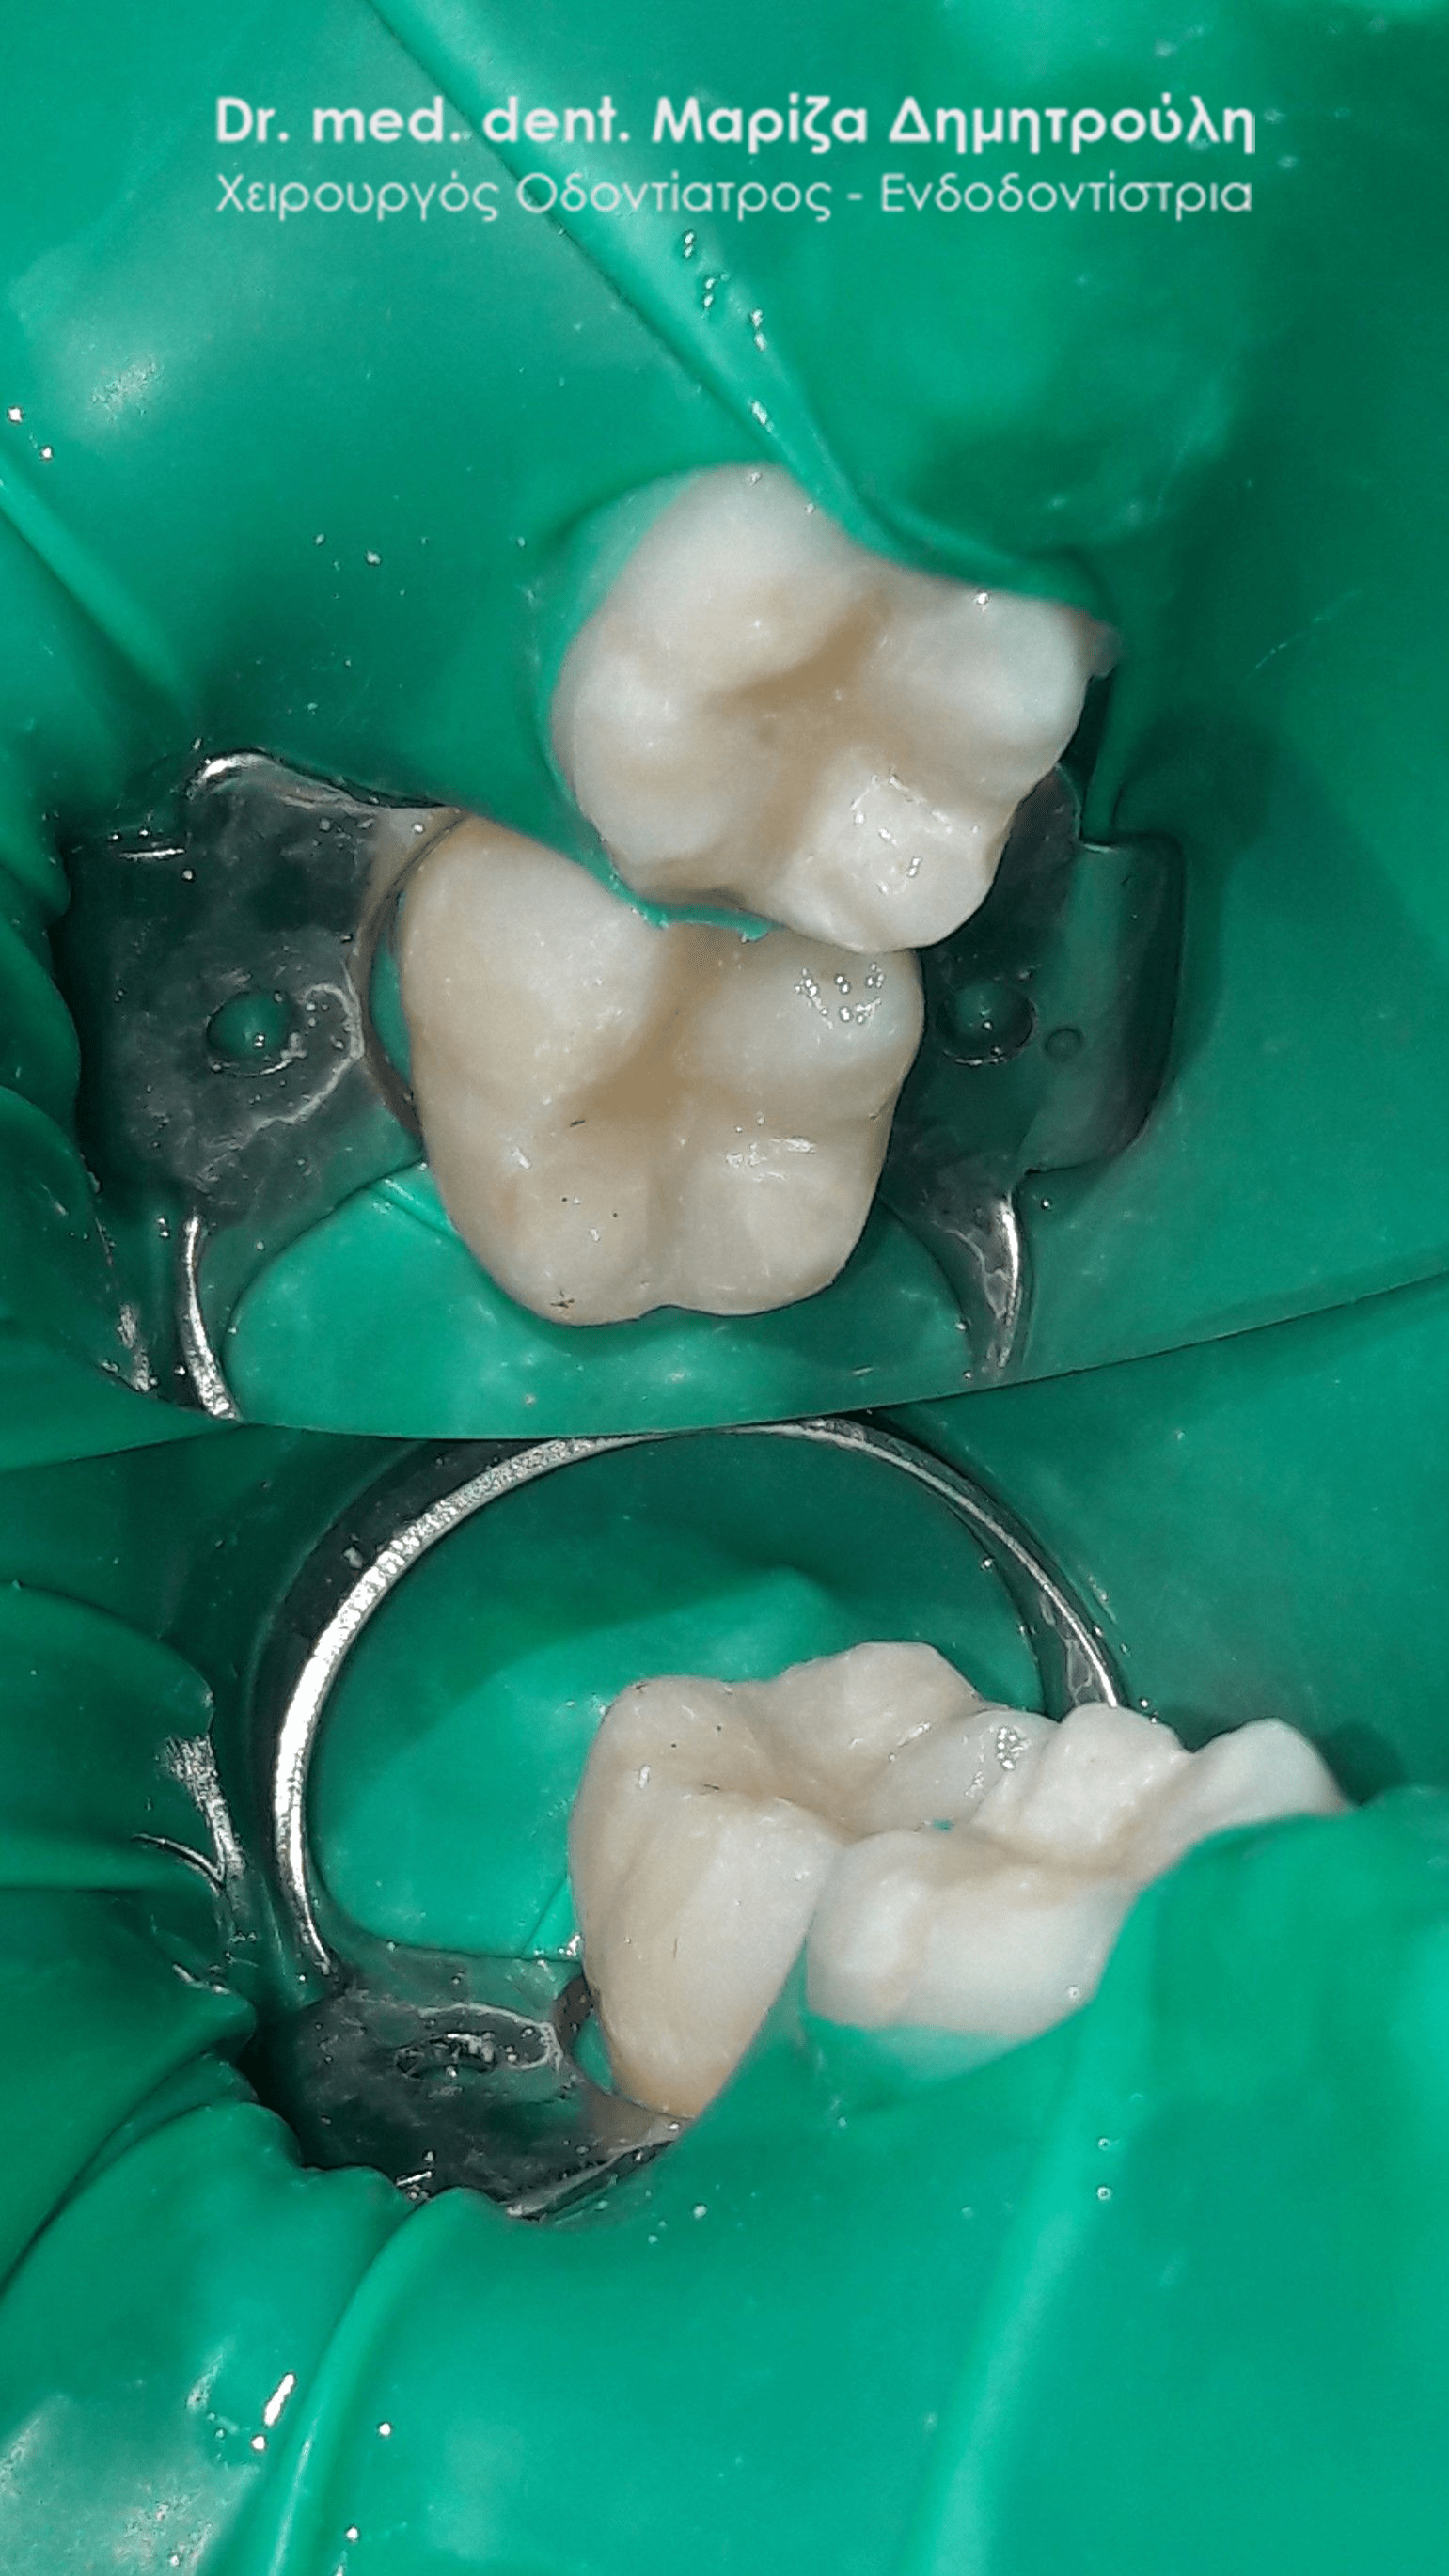

Περιστατικό – Αντικατάσταση σφραγισμάτων δοντιών

Ο ασθενής επιθυμούσε την αντικατάσταση των παλιών μαύρων σφραγισμάτων αμαλγάματος με λευκά σφραγίσματα σύνθετης ρητίνης.

Η θεραπεία πραγματοποιήθηκε με τη χρήση ελαστικού απομονωτήρα, όπως ορίζουν τα παγκόσμια πρωτόκολλα οδοντιατρικής για την αφαίρεση των μαύρων σφραγισμάτων. Οι οδοντίατροι θα ήταν καλό να χρησιμοποιούν απομονωτήτρα κατά την αφαίρεση σφραγισμάτων αμαλγάματος, έτσι ώστε ο ασθενής να εισπνέει ελάχιστα και να μην καταπίνει τον υδράργυρο, που απελευθερώνεται κατά τη διαδικασία αυτή.

Το σχέδιο θεραπείας του πρώτου γομφίου (δόντι με πολύ λευκό σφράγισμα) ήταν υπό συζήτηση, γι΄ αυτό και η αποκατάσταση του δοντιού με προσωρινό σφράγισμα.

ΠΡΙΝ

META